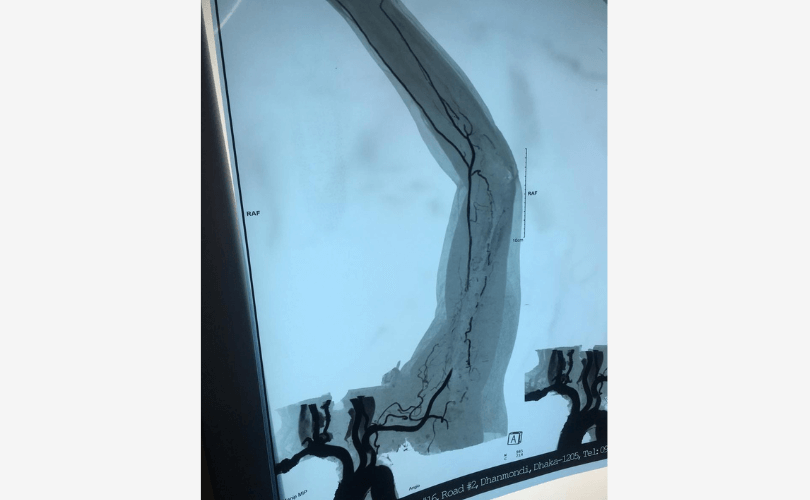

Blocked blood vessel in the right leg

Bypass surgery of the leg blood vessels